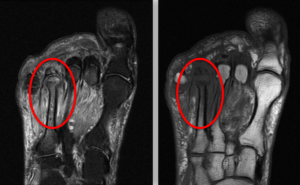

Ressonância magnética

Excelente exame para avaliar os tecidos ao redor do osso, além do aspecto ósseo, tais como inflamação. Portanto, a ressonância é o melhor exame para investigar osteomielite, principalmente nos seus estágios iniciais. Em outras palavras, a ressonância nos mostra mais do que destruição óssea, nos mostra onde há inflamação, ou seja, sinais de osteomielite aguda.